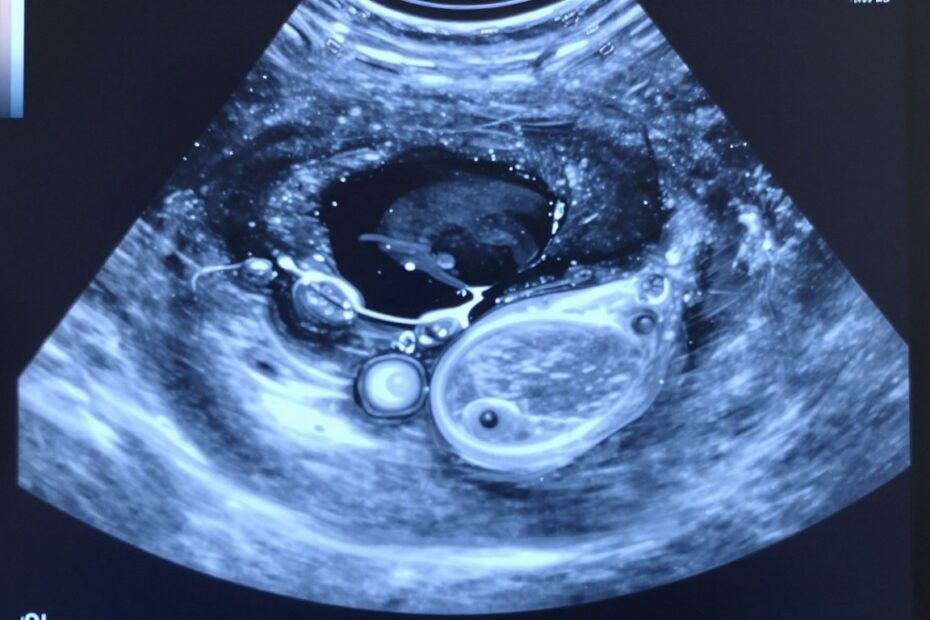

Prosta torbiel zwykle ma gładką ścianę i jednorodną zawartość, co sugeruje łagodny charakter. Zmiana złożona ma ściany przegrody lub elementy stałe i wymaga dokładniejszej oceny.

Torbiel na jajniku USG – jakie cechy ocenia lekarz podczas badania

Ocena obrazu opiera się na konkretnej liście cech, które łatwo porównać podczas kolejnych kontroli.

Checklistę badania można sprowadzić do kilku punktów:

- Wymiary — podawane w mm/cm; ważne przy decyzji o obserwacji.

- Położenie — jeden czy oba jajniki oraz relacja do sąsiednich struktur.

- Charakter treści — płyn przejrzysty vs treść niejednorodna czy z elementami litymi.

- Ściany i przegrody — grubość, nieregularność, liczba komór.

- Unaczynienie (Doppler) — obfite naczynia mogą zwiększyć podejrzenie.

Prosta, jednokomorowa zmiana zwykle sugeruje łagodny przebieg. Obecność przegród, wyrośli brodawkowatych lub elementów stałych zwiększa potrzebę dalszej diagnostyki.

W opisie warto zanotować takie terminy jak wielokomorowa, wyrośla brodawkowate czy płyn w zatoce Douglasa. Lekarz zawsze zestawi obraz z wiekiem i objawami pacjentki.

Rodzaje torbieli jajnika i ich typowy obraz w USG

Krótka mapa rozpoznań pokazuje, jak różne typy wyglądają w obrazie i skąd biorą się nazwy w opisie.

Torbiel pęcherzykowa (czynnościowa) to niepęknięty pęcherzyk Graafa. Zwykle jest prosta, wypełniona płynem i ma gładkie ściany. Pojawia się w cyklu i często ustępuje samoistnie.

Torbiel ciałka żółtego powstaje po owulacji. Zależna od zmian hormonalnych, może być większa i mieć bardziej złożony obraz. Często wiąże się z ciałka żółtego, które nie cofa się prawidłowo.

Torbiel krwotoczna zawiera krew po uszkodzeniu naczynia. W obrazie treść wygląda niejednorodnie i czasem ma cienkie przegrody.

Torbiel endometrialna (tzw. „czekoladowa”) ma gęstą, echogeniczną zawartość. Często towarzyszy endometriozie i może wpływać na płodność.

Torbiel dermoidalna (potworniak dojrzały) zawiera elementy skórne, włosy lub zęby. Ze względu na nietypową zawartość częściej wymaga leczenia zabiegowego.